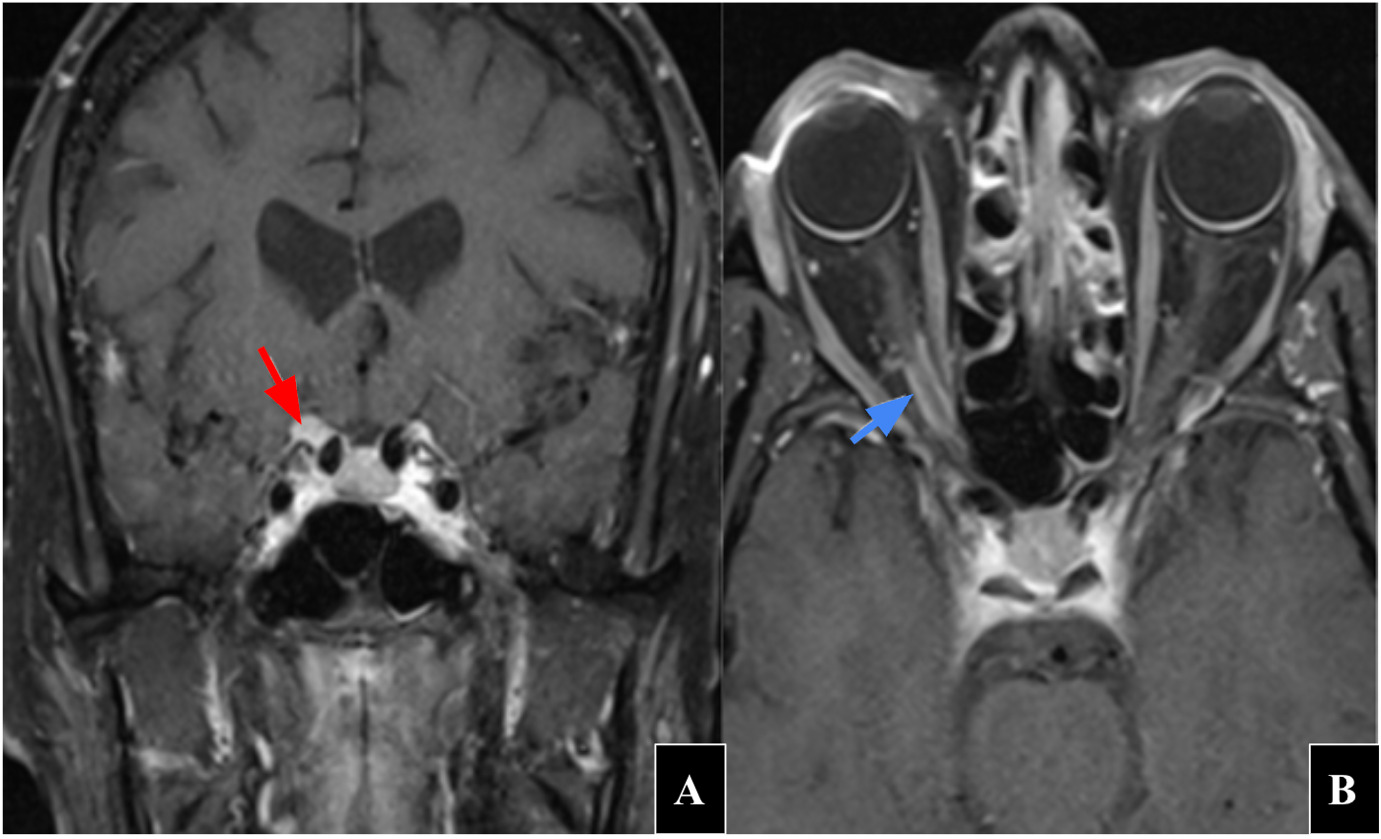

Her laboratory workup was unremarkable for any inflammatory or infectious etiologies. Her brain magnetic resonance image with and without contrast revealed scattered nonspecific punctate and patchy foci of T2 hyperintense signal without mass effect in the bilateral subcortical and periventricular white matter and corona radiata, likely due to minimal chronic microvascular ischemic changes. The report also stated T2 hyperintense signal present in the cortex of the posterior left frontal lobe with associated volume loss likely reflecting small chronic infarction. An exact etiology for her vision loss in the right eye was not noted on the magnetic resonance image brain report. However, upon review of the images and discussion with the radiologist, it was determined that there was some increased T2 signal around the right optic nerve. A dedicated orbital magnetic resonance image with and without contrast was ordered. The orbital magnetic resonance image revealed a 9 × 11 × 5 mm type III anterior clinoidal meningioma extending into the optic canal along the optic nerve sheath (Figure 5). Based on these findings, she was scheduled to see a neurosurgeon and underwent a right fronto-orbital craniotomy with tumor resection which was completed without complications. She also discontinued medroxyprogesterone therapy.